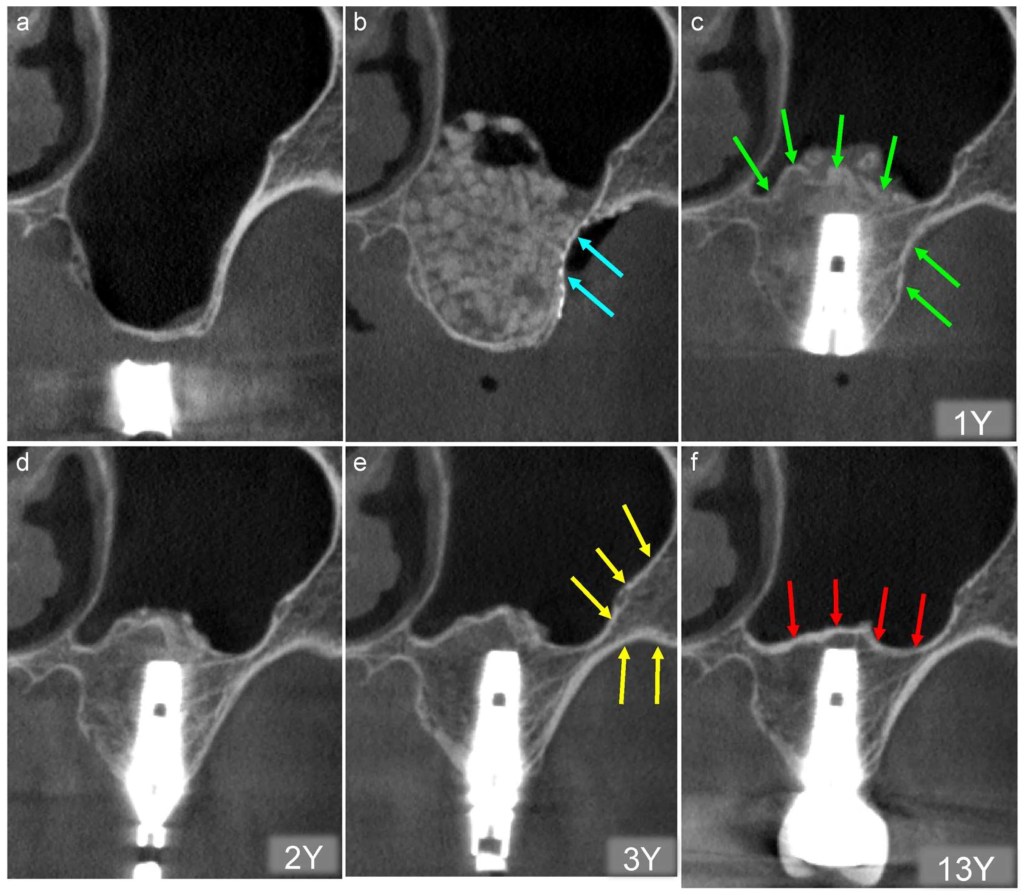

需先清創、讓骨頭恢復癒合數月後,重新評估齒槽骨狀況再進行植牙或合併其他術式(如:鼻竇頂骨補骨手術、鼻竇開窗齒槽骨重建手術、自體齒槽骨重建手術…等),成功率才會高。